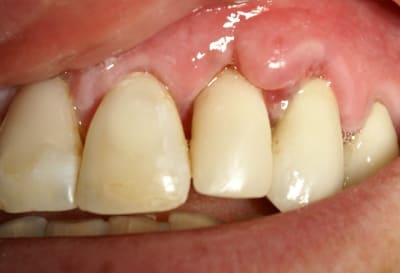

Tout à fait d'accord growler et c'est d'ailleurs ce que l'on peut voir sur le cas suivant. Fracture radiculaire, aucune infection periradicualire. Extraction et implantation immediate. Espace existant entre l'implant et l'alvéole est comblé par du BioOss. Un logement sous gingival est formé en vestibulaire et palatin de facon à pouvoir recouvrir le tout par BioGide et un conjonctif enfoui.

L'implant est de 15mm mais l'alvéole était large et 50% environ de la surface implantaire n'était en contact qu'avec du BioOss. J'ai pour cela préféré enfouir.